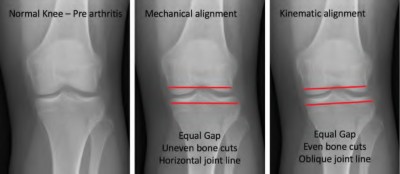

Figure A demonstrates and AP radiograph of the knee showing end-stage arthritis with severe lateral compartment narrowing.